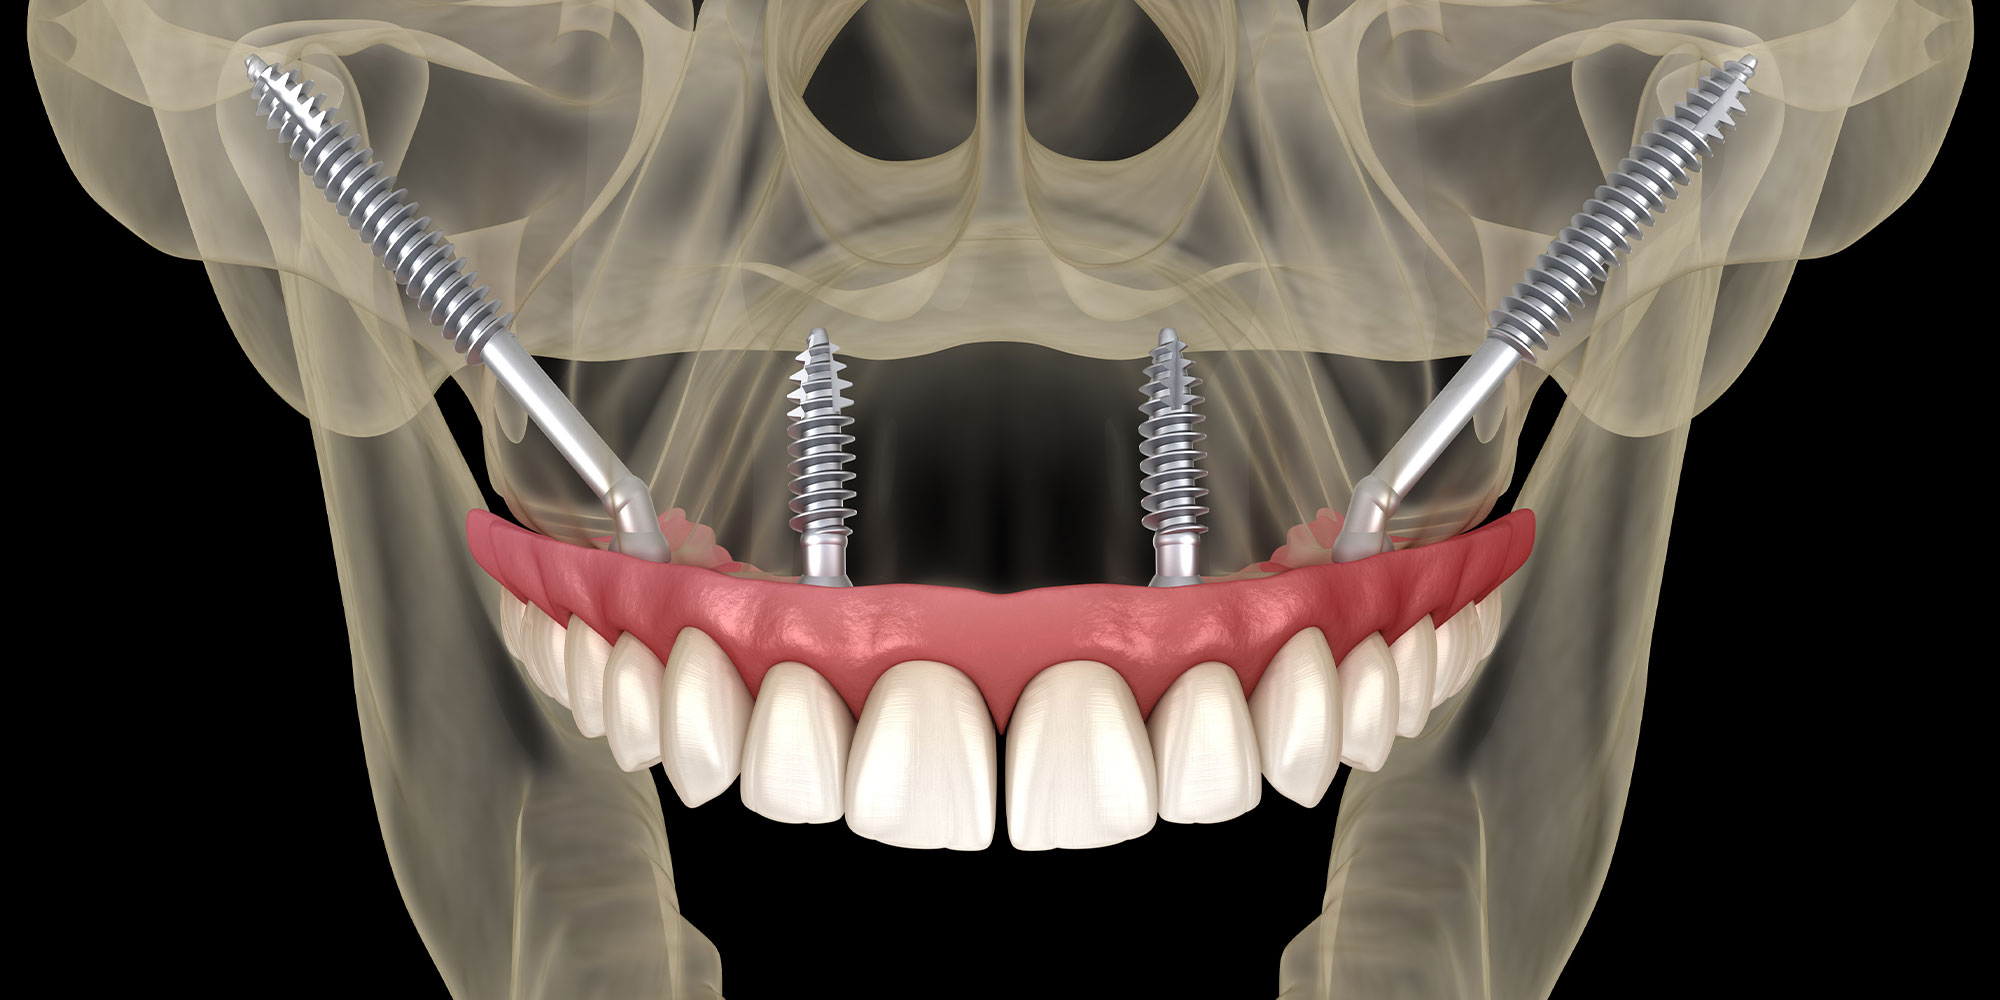

Enquanto o All-on-4 (ou All-on-Four) é indicado para pacientes com [...]

As doenças conhecidas por atrofia de maxila e atrofia de [...]